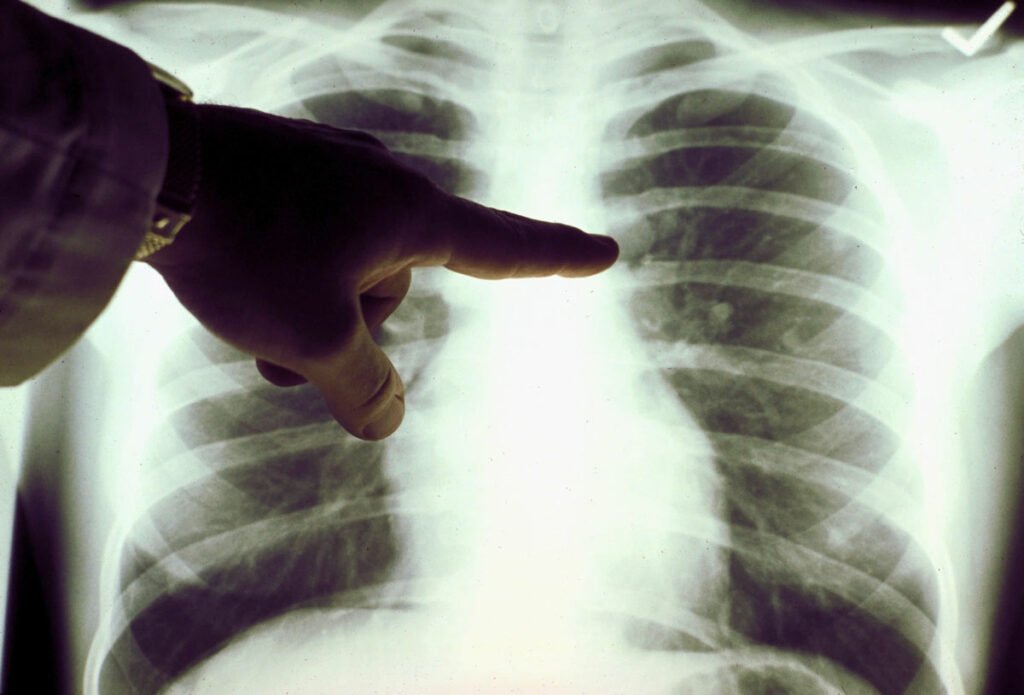

[ad_1] نوشته و ویرایش شده توسط مجله ی کویر دانش سرطان ریه در صدر فهرست مرگومیر ناشی از سرطان در سراسر دنیا قرار دارد. نتایج آزمایش یک قرص تازه سرطان ریه روی افراد مبتلا به شایعترین نوع این سرطان مشخص…